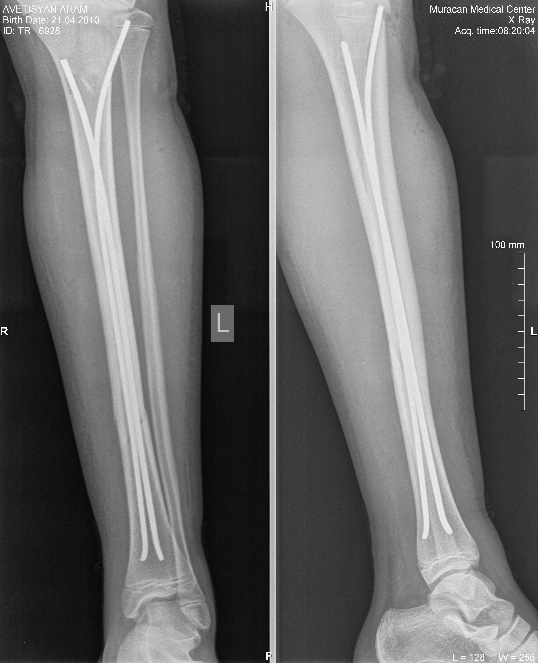

Այս ուսումնասիրությունը հիմնված է 21 հիվանդների (17 տղա, 4 աղջիկ) շարունակական խմբի բուժման արդյունքների վերլուծության վրա, որոնք ենթարկվել են տիտանե էլաստիկ մեխերով վիրահատության։ Հիվանդների տարիքը եղել է 4 տարեկանից մինչև 16 տարեկան։ 9 երեխայի մոտ կոտրվածքի պատճառ է հանդիսացել ձեռքի վրա անկումը, մնացածի մոտ կոտրվածքն առաջացել է վերջույթի ոլորման արդյունքում, վնասվածքի մեխանիզմը եղել է ուղիղ: 19 դեպքերում կոտրվածքները եղել են փակ, իսկ 2 դեպքում՝ բաց։ Ըստ վնասվածքի տեղայնացման՝ դրանք եղել են դիաֆիզար կոտրվածքներ (15 դեպք), պրոքսիմալ մետաֆիզի մակարդակի կոտրվածք (3 դեպք) և հեռավոր մետաֆիզի՝ (3 դեպք): Կոտրվածքային գծի բնույթի համաձայն՝ դիաֆիզային կոտրվածքներից հայտնաբերվել են 6 լայնակի, 4 թեք, 5 պտուտակաձև։ Մի տղայի մոտ (4 տարեկան), որի մոտ առկա էր սրունքի մ/3-ի բաց թեք կոտրվածք տեղաշարժով և մաշկի մինուս հյուսվածքներով, կատարվել է նաև վերքերի առաջնային վիրաբուժական մշակում և կարում՝ ռետինյա արտաթորիչներով։ Սակայն մի քանի շաբաթ անց սկսվել է մաշկի նեկրոզ։ Այդ իսկ կապակցությամբ կատարվել է երկրորդ վիրահատական միջամտությունը։ Կատարվել է մաշկի աուտոտրանսպլանտացիա։ Մաշկի կտորները վերցվել են առողջ ազդրի առաջային մակերեսից: (Նկ 1)

Օգտագործված մեթոդները համահունչ էին հեղինակների նկարագրած վիրաբուժական տեխնիկայի հետ: Հիմնական սկզբունքներն էին՝ ձողերի տրամագիծը, որը համապատասխանում է մեդուլյար լուսանցքի տրամագծի 30-40% -ին, ձողերի թեքությունները նույնական են, բայց հակառակ ուղղորդված և տեղակայված են կոտրվածքի մակարդակում, հարմարեցված վիրաբուժական գործիքների օգտագործումը: